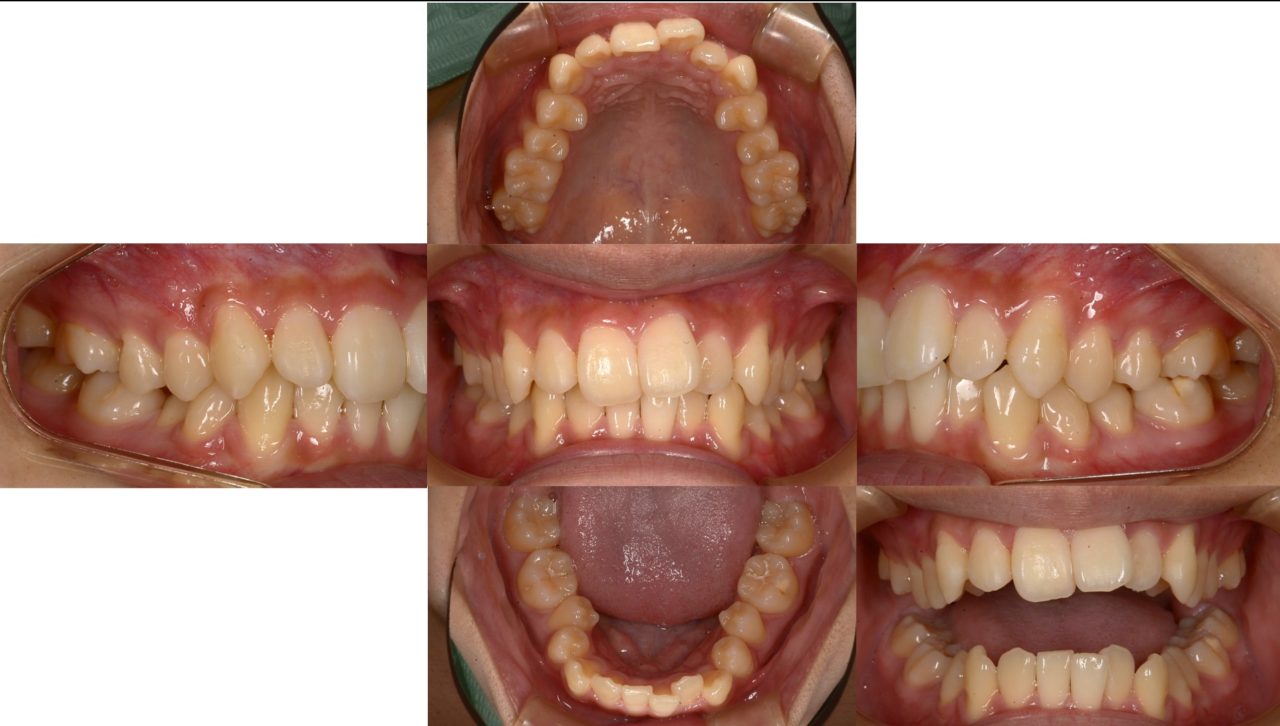

Before

2023.2.2 初診

上下顎ともに前歯に歯列不正を認める